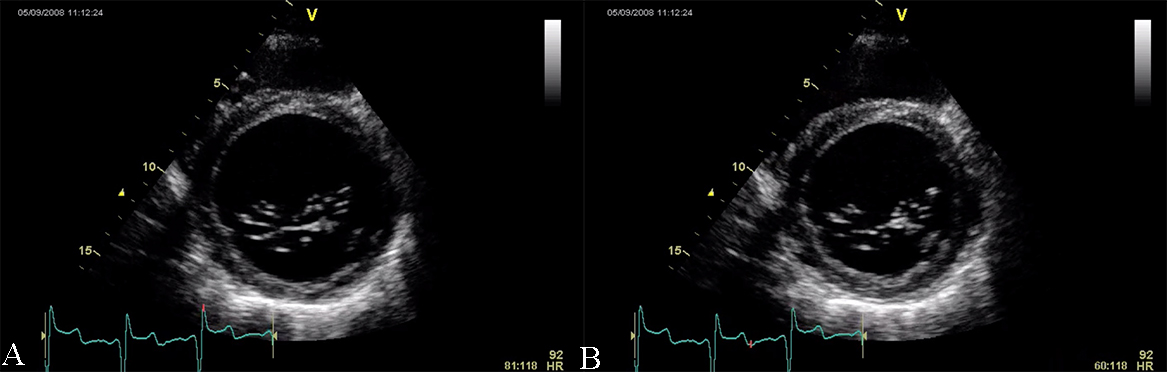

Restrictive cardiomyopathy (RCM) is characterized by non-dilated ventricles, mild or no myocardial hypertrophy with impaired ventricular filling, thus it is defined by abnormal ventricular diastolic function with a normal size LV (see Fig. 8). In the early stages of the disease, the systolic function of the LV is also normal [38].

Fig. 8.The echocardiographic aspect of RCM in an elderly patient presenting with signs and symptoms of heart failure. Apical 4 chamber view showing severe biatrial enlargement, with left atrial thrombus and non-dilated left and right ventricles.